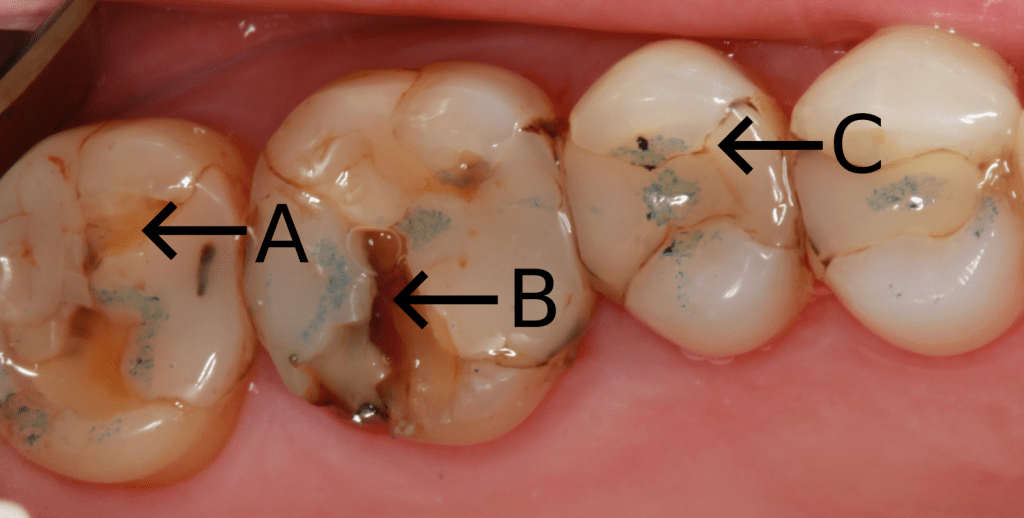

Restoring a tooth does not eliminate the carious process if the oral environment is left unchanged. Poor oral hygiene, defective restoration margins, open contacts, overhangs, inferior dental materials, and fractured fillings can all lead to decay. Secondary caries is mainly seen at the interface of the filling and tooth. Hydrolysis of the resin bond used in composite leads to marginal leakage which is visible as marginal staining. Continued breakdown and bacterial ingress lead to caries in this area. Marginal staining is a sign of restorative failure.

A. Sclerotic dentine, arrested caries

B. Secondary caries

C. Marginal leakage